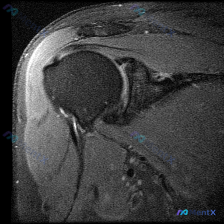

整理到一份肩关节影像病例资料,先放单张轴位T2加权MRI: > 影像基础:肩关节轴位T2加权序列,可见肱骨头、关节盂、肩胛下肌等结构,前下盂唇区域存在局灶性高信号影,肱骨头骨皮质完整,无明显关节积液或巨大占位。 想问问大家,仅根据这张图像的表现,第一反应会先往哪个方向考虑?有没有需要特别注意的鉴别点...

整理了一份肩关节MRI的病例资料,临床申请的检查目的是排查盂唇病变,不过仔细阅片后发现核心异常好像不在盂唇那边? 先放已明确的影像基础信息: - 序列修正:初始标注为T1序列,实际影像符合质子密度压脂(PD FS)或T2压脂序列特征,对积液、肌腱损伤敏感 - 核心可见表现:肱骨大结节处肌腱信号异常、...